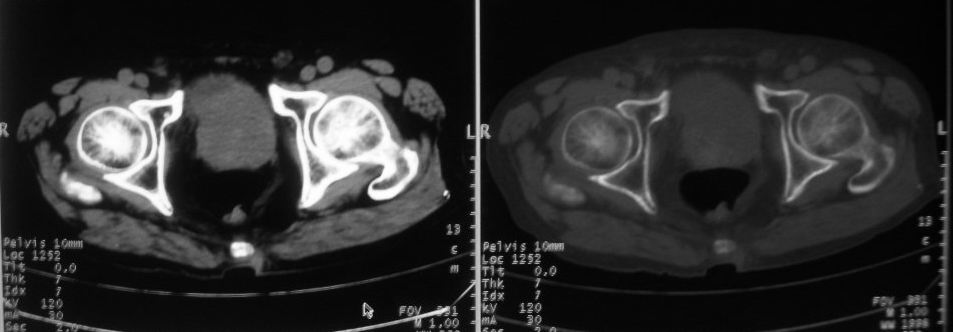

以下是引用zjzjr在2008-10-3 12:59:00的发言:[br]前列腺癌伴左髂骨\\腰椎转移可能性大.

以下是引用卜一在2008-10-3 13:40:00的发言:[br]前列腺癌!左髂骨\\腰椎转移?建议行全身骨扫描!

以下是引用深泽交通医院在2008-10-3 15:33:00的发言:[br]前列腺实性增大伴分叶状,与包膜间隙境界不清;椎体松质区间结节样密度影,考虑:前列腺癌,并椎体成骨性转移